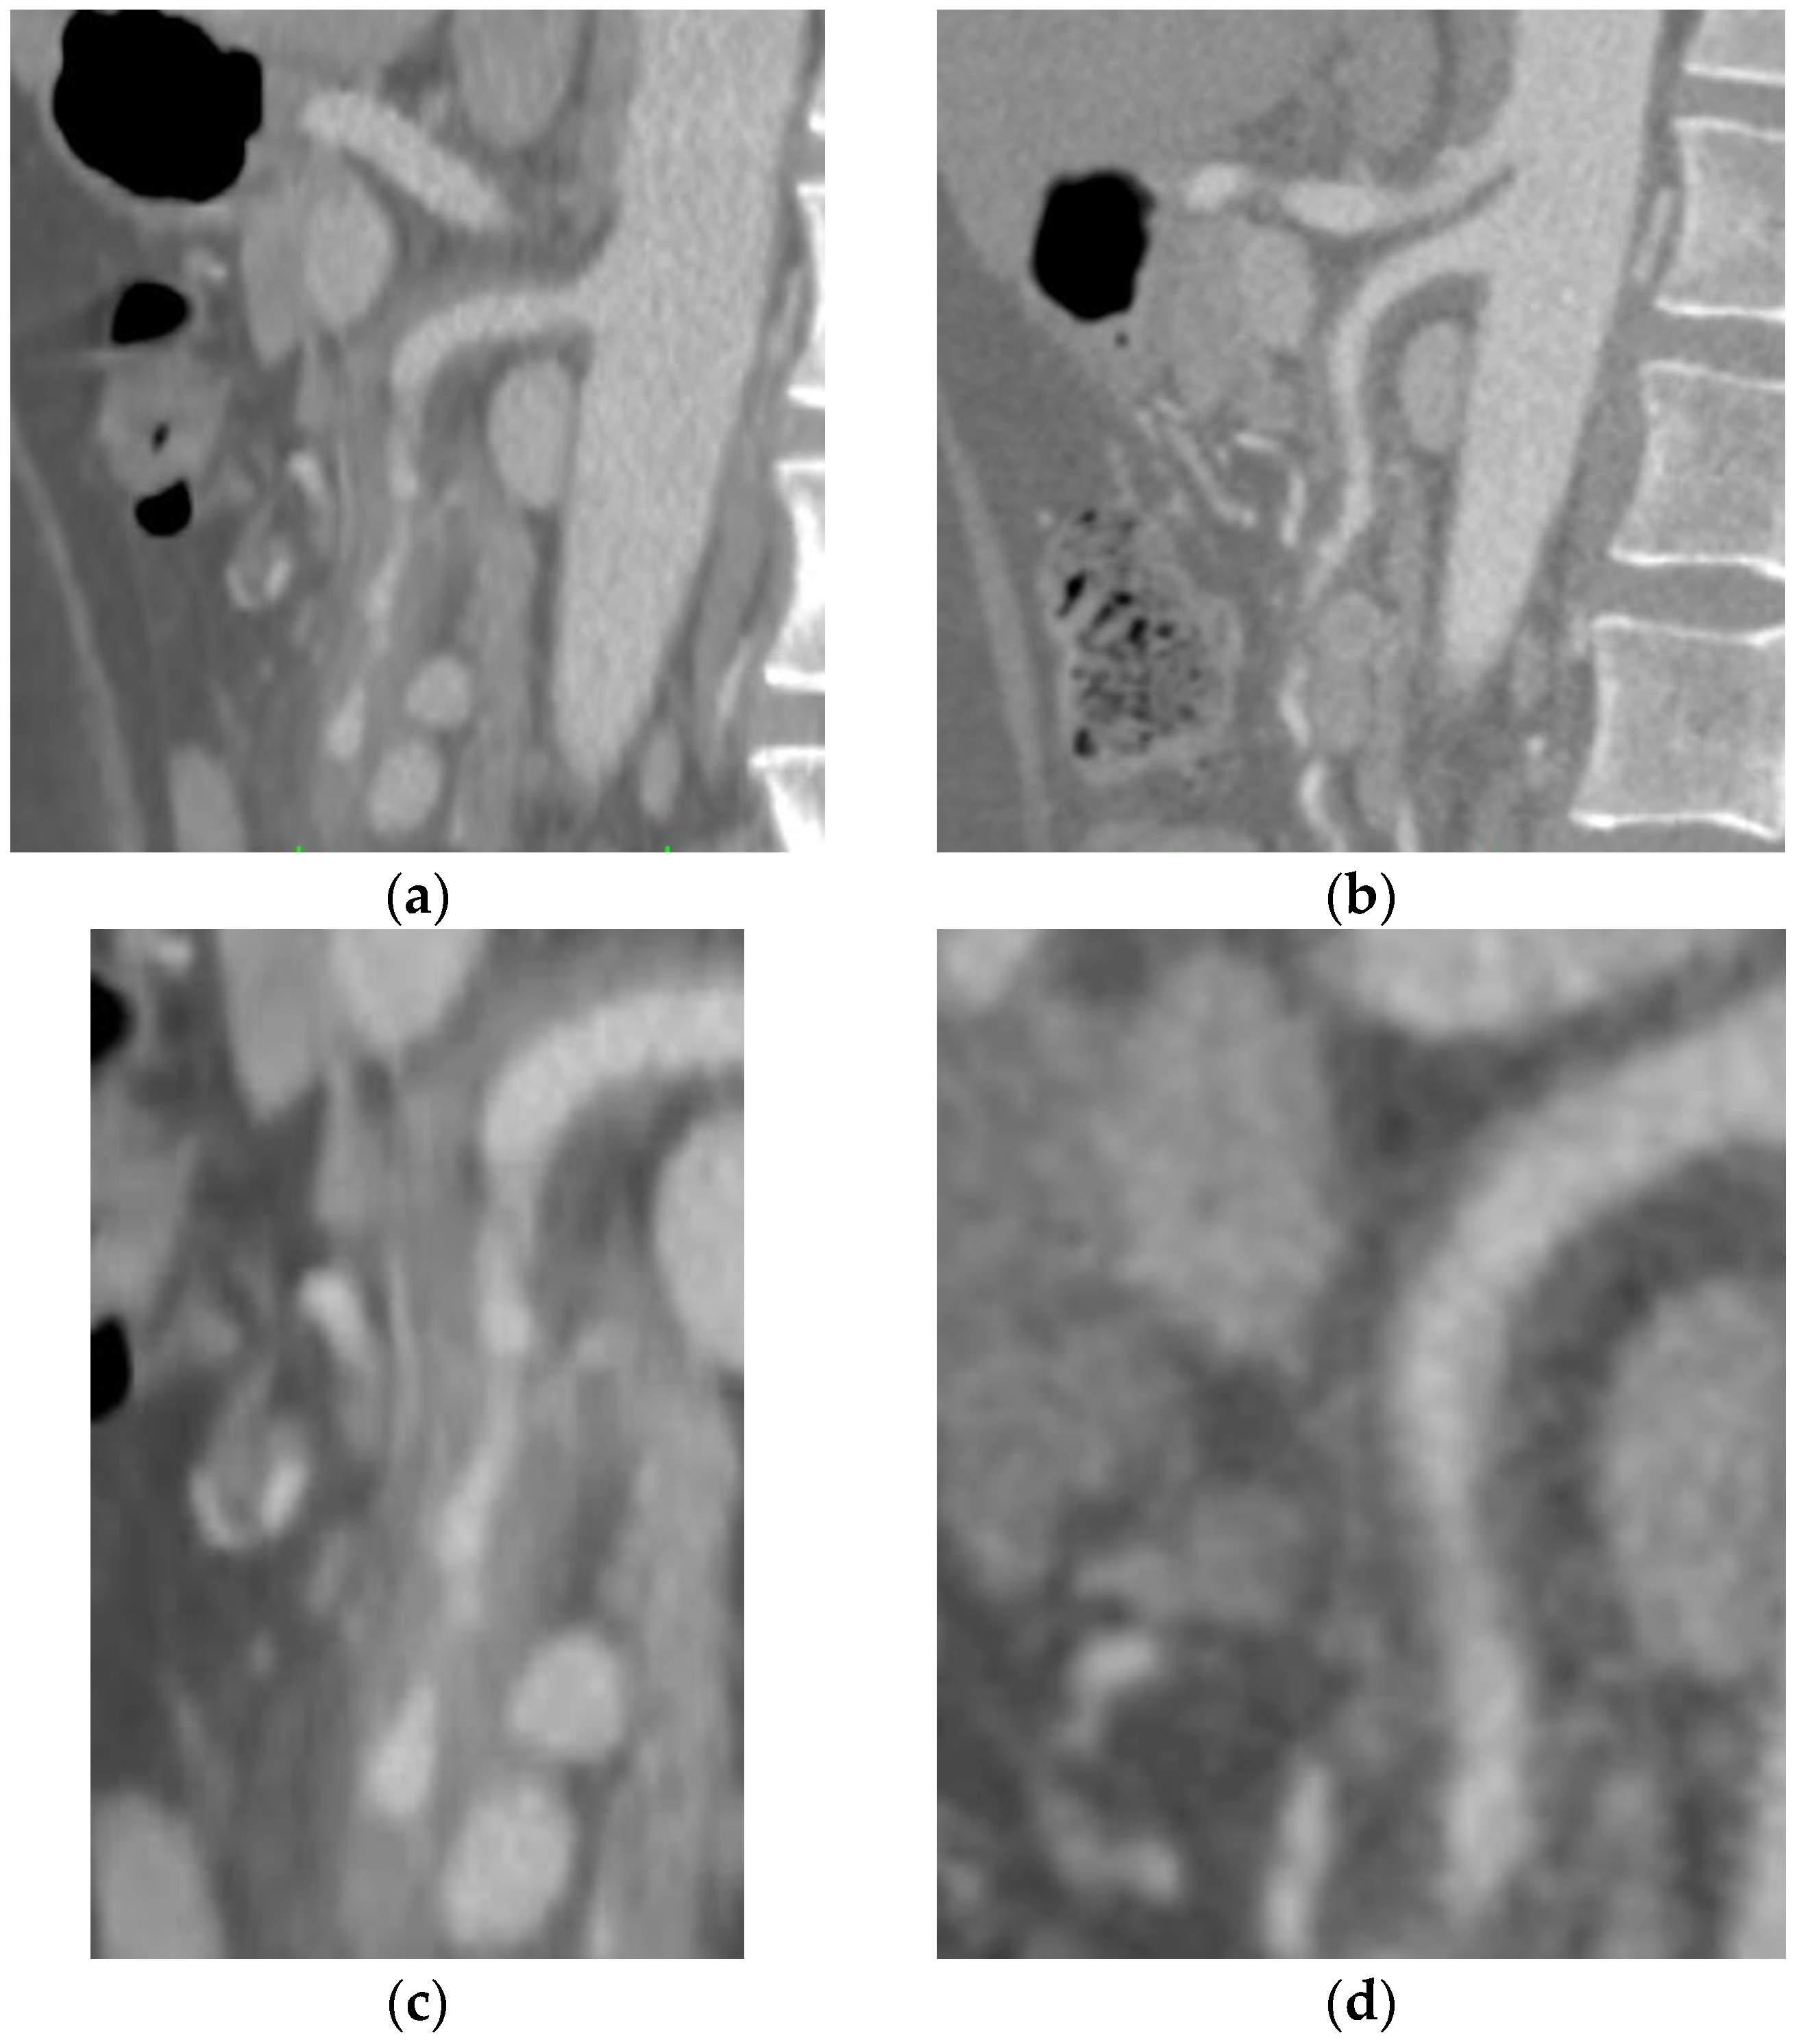

2.2. Case B